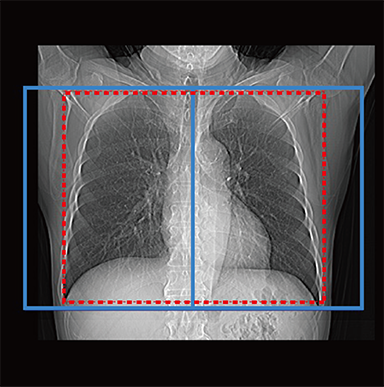

chest

Red: automatically set position, Blue: automatically set position + margin setting position